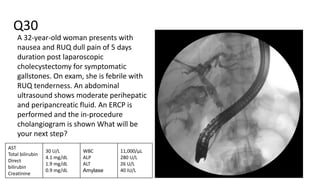

Q30

A 32-year-old woman presents with

nausea and RUQ dull pain of 5 days

duration post laparoscopic

cholecystectomy for symptomatic

gallstones. On exam, she is febrile with

RUQ tenderness. An abdominal

ultrasound shows moderate perihepatic

and peripancreatic fluid. An ERCP is

performed and the in-procedure

cholangiogram is shown What will be

your next step?

AST

Total bilirubin

Direct

bilirubin

Creatinine

30 U/L

4.1 mg/dL

1.9 mg/dL

0.9 mg/dL

WBC

ALP

ALT

Amylase

11,000/μL

280 U/L

26 U/L

40 IU/L

● Place a stent while in ERCP.

Q30 A 32-year-old womanpresents with nausea and RUQ dull pain of 5 days duration post laparoscopic cholecystectomy for symptomatic gallstones. On exam, she is febrile with RUQ tenderness. An abdominal ultrasound shows moderate perihepatic and peripancreatic fluid. An ERCP is performed and the in-procedure cholangiogram is shown What will be your next step? AST Total bilirubin Direct bilirubin Creatinine 30 U/L 4.1 mg/dL 1.9 mg/dL 0.9 mg/dL WBC ALP ALT Amylase 11,000/μL 280 U/L 26 U/L 40 IU/L

• 142.

● Place astent while in ERCP. ● Post choleycystectomy biliary leak.